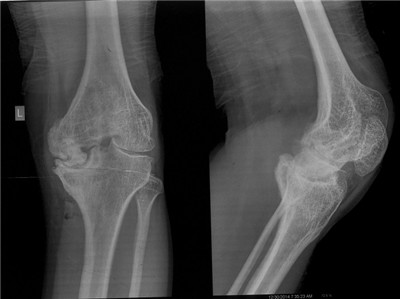

近日在骨二科徐思越副主任医师治疗组收治的一例血友病性关节炎患者的膝关节置换术中,一如既往地贯彻了个性化治疗、术前周密准备的传统。这位青年男性患者数年前因为血友病性巨大假瘤侵蚀膝关节骨质,不得不行右下肢膝上截肢,现在又由于严重的左膝血友病性关节炎承受着严重的膝关节疼痛。这位患者的膝关节骨质发育不良,且胫骨侧骨质严重缺损,并伴有屈曲挛缩畸形。对这样特殊的血友病性关节炎病例,是行技术要求高、围手术风险大的膝关节置换术;还是做风险较小,比较“稳妥”的膝关节融合术?

我们充分站在患者角度思考,考虑到膝关节融合术会给一个已经接受过对侧截肢手术青年患者,在未来漫长生涯中带来的巨大不便。我们决定,接受挑战,优先考虑膝关节置换术。